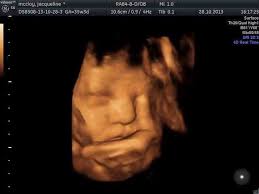

4D Ultrasound Pictures 35 Weeks - Got My 3d 4d Ultrasound At 35 Weeks Too Cute Not To Share January 2020 Babies Forums What To Expect - You'll notice that what you see varies a lot by the number of weeks of gestation.. Even if they're squished and you don't get the best pictures. They were the first to tell me that i was having a baby boy at 16 weeks. The way 4d/3d works is it sends sound waves into the uterus. Baby's first photos 112 e. The best proof is our gallery of weekly 3d ultrasound images taken from 13 weeks and until up to 39 weeks.

Baby impressions is an elective 3d 4d ultrasound imaging facility. Fetal measurements (by request) hear & see baby's heartbeat. 3d & 5d ultrasound images and 4d ultrasound video can be obtained at any stage. Baby's estimated weight and position. 30 weeks is best for 3d/4d images of what your baby will look like after it is born. Water can improve the quality of an ultrasound. At this stage, the baby has put on some weight and filled out to make features more visible, yet still enough fluid in front of baby's face to obtain great images. You'll notice that what you see varies a lot by the number of weeks of gestation. It was a very special day for my husband and i. In addition to 3d 4d ultrasound, baby bloom is known for our spectacular hd live ultrasound imaging. We do not perform medical ultrasounds. When i was 31 weeks i went back for our first 3d/4d ultrasound and it was even more special being able to see my son's face for the very first time. Book now *free rescan if face can't be seen at all.

In these final weeks before your baby's birth, several subtle changes are taking place that will prepare. 4d or 4 dimensional scans build on the technology of 3d scans. Video recording of your session on babyflix. Each week in pregnancy can look slightly different. 3d/4d & hd ultrasound 8 week baby in 2d, 3d/4d & hd ultrasound pictures 12 week baby in 3d 4d baby ultrasound pictures 15 week baby in 2d, 3d/4d & hd ultrasound pictures 23 week baby in 3d 4d & hdlive baby pictures 13.5 weeks 14 weeks 15 weeks 15.2 weeks twins 16 weeks 18 weeks 22 weeks 24 weeks 27 weeks 29 weeks 30 weeks 31 weeks with.